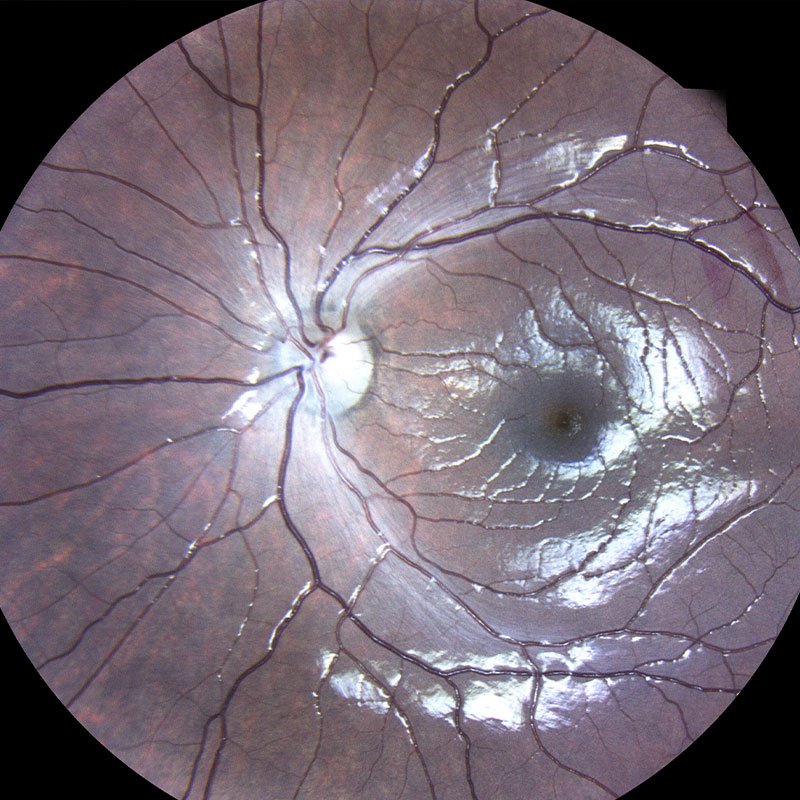

Η συγγενής φυλοσύνδετη ρετινόσχιση είναι μια κληρονομούμενη δυστροφία του αμφιβληστροειδή η οποία οφείλεται σε μεταλλάξεις του γονιδίου RS1. Εμφανίζεται με μείωση της κεντρικής όρασης σε νεαρούς άρρενες. Ο ηλεκτροφυσιολογικός έλεγχος (Ηλεκτροαμφιβληστροειδογράφημα) είναι πολύτιμος για τη διάγνωση της νόσου μιας και έχει χαρακτηριστικά ευρήματα στις καταγραφές ενώ ο γενετικός έλεγχος ταυτοποιεί τη διάγνωση.